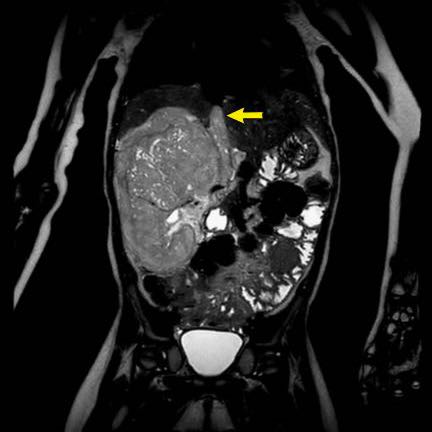

Ca lâm sàng 1

Hình ảnh chuỗi xung T2W mặt phẳng coronal cho thấy một khối u không đồng nhất ở thận trái với các thành phần nang nhỏ.

Khối u ngấm thuốc kém hơn so với phần nhu mô thận bình thường còn lại ở ngoại vi.

Các thành phần đặc của khối u cho thấy hạn chế khuếch tán rõ rệt (mũi tên).

Đây là u Wilms ở bé trai năm tuổi. Hóa trị tiền phẫu được thực hiện theo phác đồ Umbrella của SIOP-RTSG, sau đó tiến hành cắt thận.